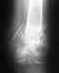

Вчера прислал свежий рентген. Посмотрите пожалуйста.

Также прилагаю снимки сделанные два месяца раннее.

Такое положение было бы как-то приемлемо в ближайшие 2-3 недели после травмы. Почему в течение первого месяца не был выполнен переход с временной наружной фиксации на окончательную внутреннюю? Или хотя бы аппарат Илизарова?

Неизвестно, каково состояние мягких тканей поврежденного сегмента. Если явного нагноения зоны перелома нет, желательно бы организовать, пусть и запоздало, но замену наружного фиксатора на внутрикостный. Потребуется удалить обломки сломанных стержней. Лучше использовать интрамедуллярный штифт с антибактериальным покрытием.